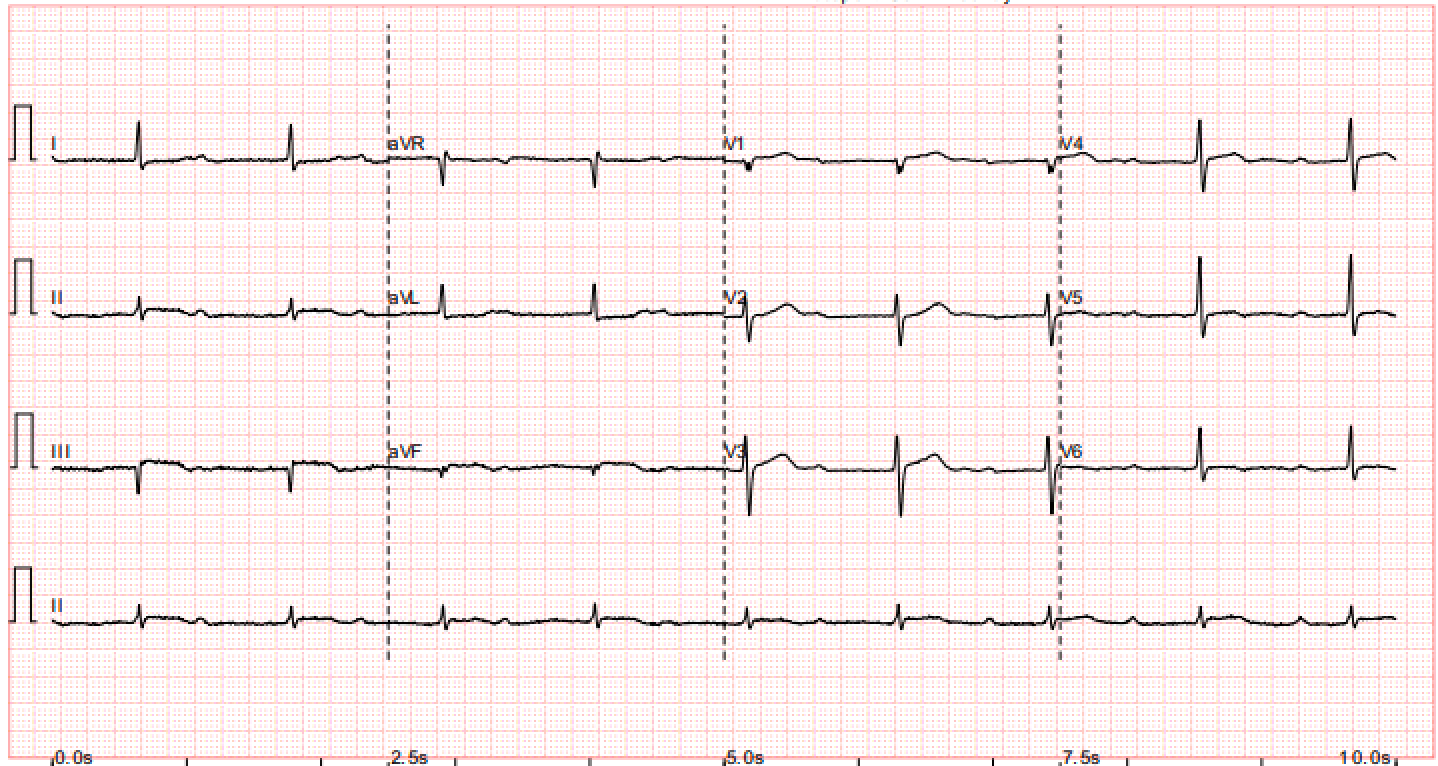

Mr A is a 45 year old construction site worker with unremarkable past health. He is active smoker with 30 pack years. He has no family history of premature CAD. He presented with sudden onset of severe chest pain at 1am. Prehospital ECG showed complete heart block, 50 beats per min, ST segment elevation at inferior leads with right side involvement.

His vitals are stable: BP 160/116 P53 SpO2 98% RA Hstix 15

Bloods tests are grossly unremarkable. Troponin 218 (<= 34.2) CK 412

CXR is clear

Echo shows impaired LV systolic function, EF ~ 45%, inferior wall hypokinesia. Dilated RV Mild MR. no AR. mod TR. No pericardial effusion.PPCI is activated. He is sent to catherization lab immediately.